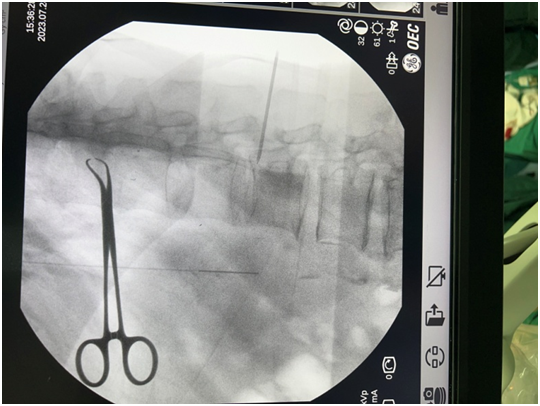

7 月 25 日,经过充分准备、C 型臂定位,在全麻下穿刺针进入蛛网膜下腔退出针芯后,脑脊液回流通畅,植入并固定好导管,在左侧腋前线平肋弓处植入皮下注射装置,缝合微创小伤口,手术完成。